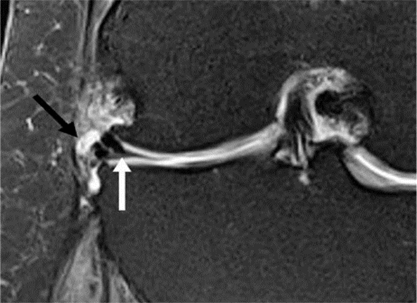

Hình 4. Rách sụn chêm, nang sụn chêm. Hình ảnh coronal xóa mỡ có u nang nhỏ (mũi tên đen) tiếp giáp với thân của sụn chêm bên có vết rách liên quan đến sụn chêm (mũi tên trắng)